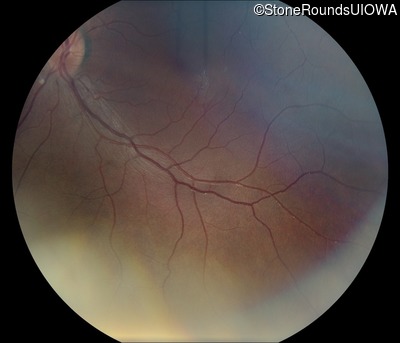

Fundus Montage - Right - 20/50 -1

Exemplar